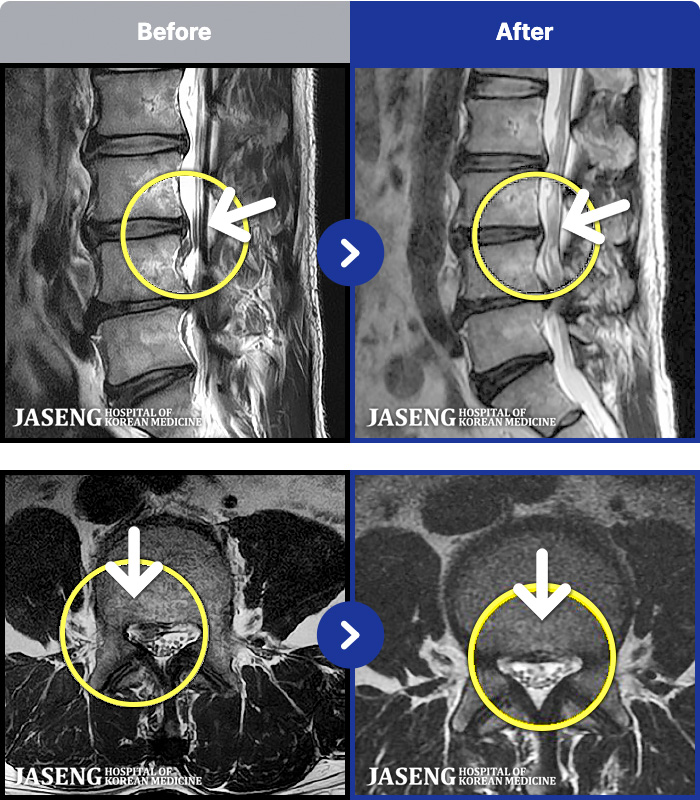

54 MRI ũ ʸ Ȯϼ.

ȯںп Ǹ ǿ ԿǾ, ο ġ ۿ Ƿ ġḦ Ͻñ ٶϴ.